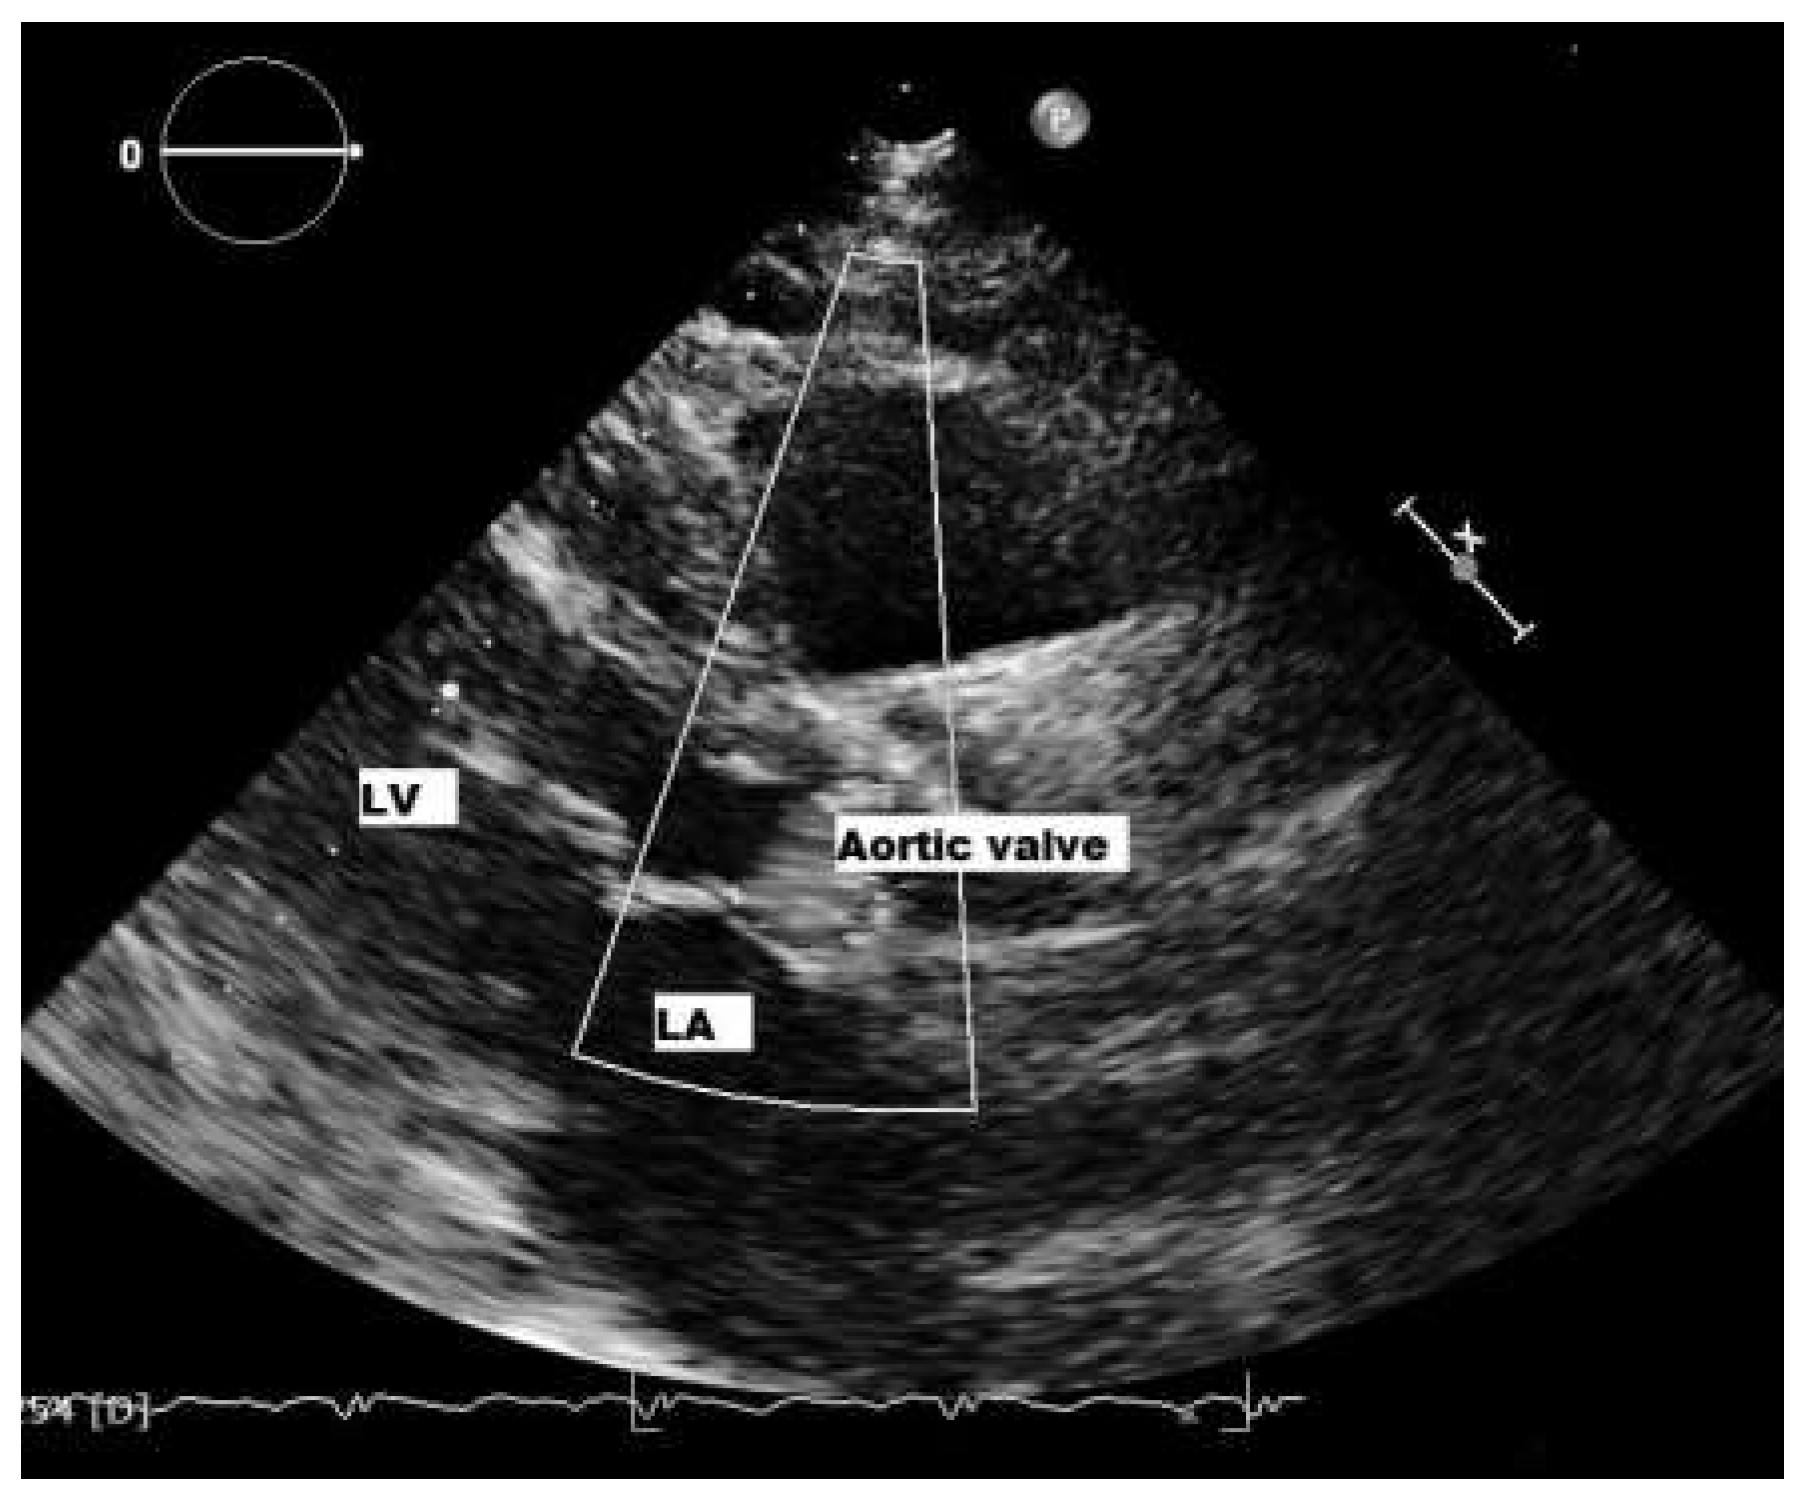

Patient

Six-month follow-up

Sixteen-month follow-up